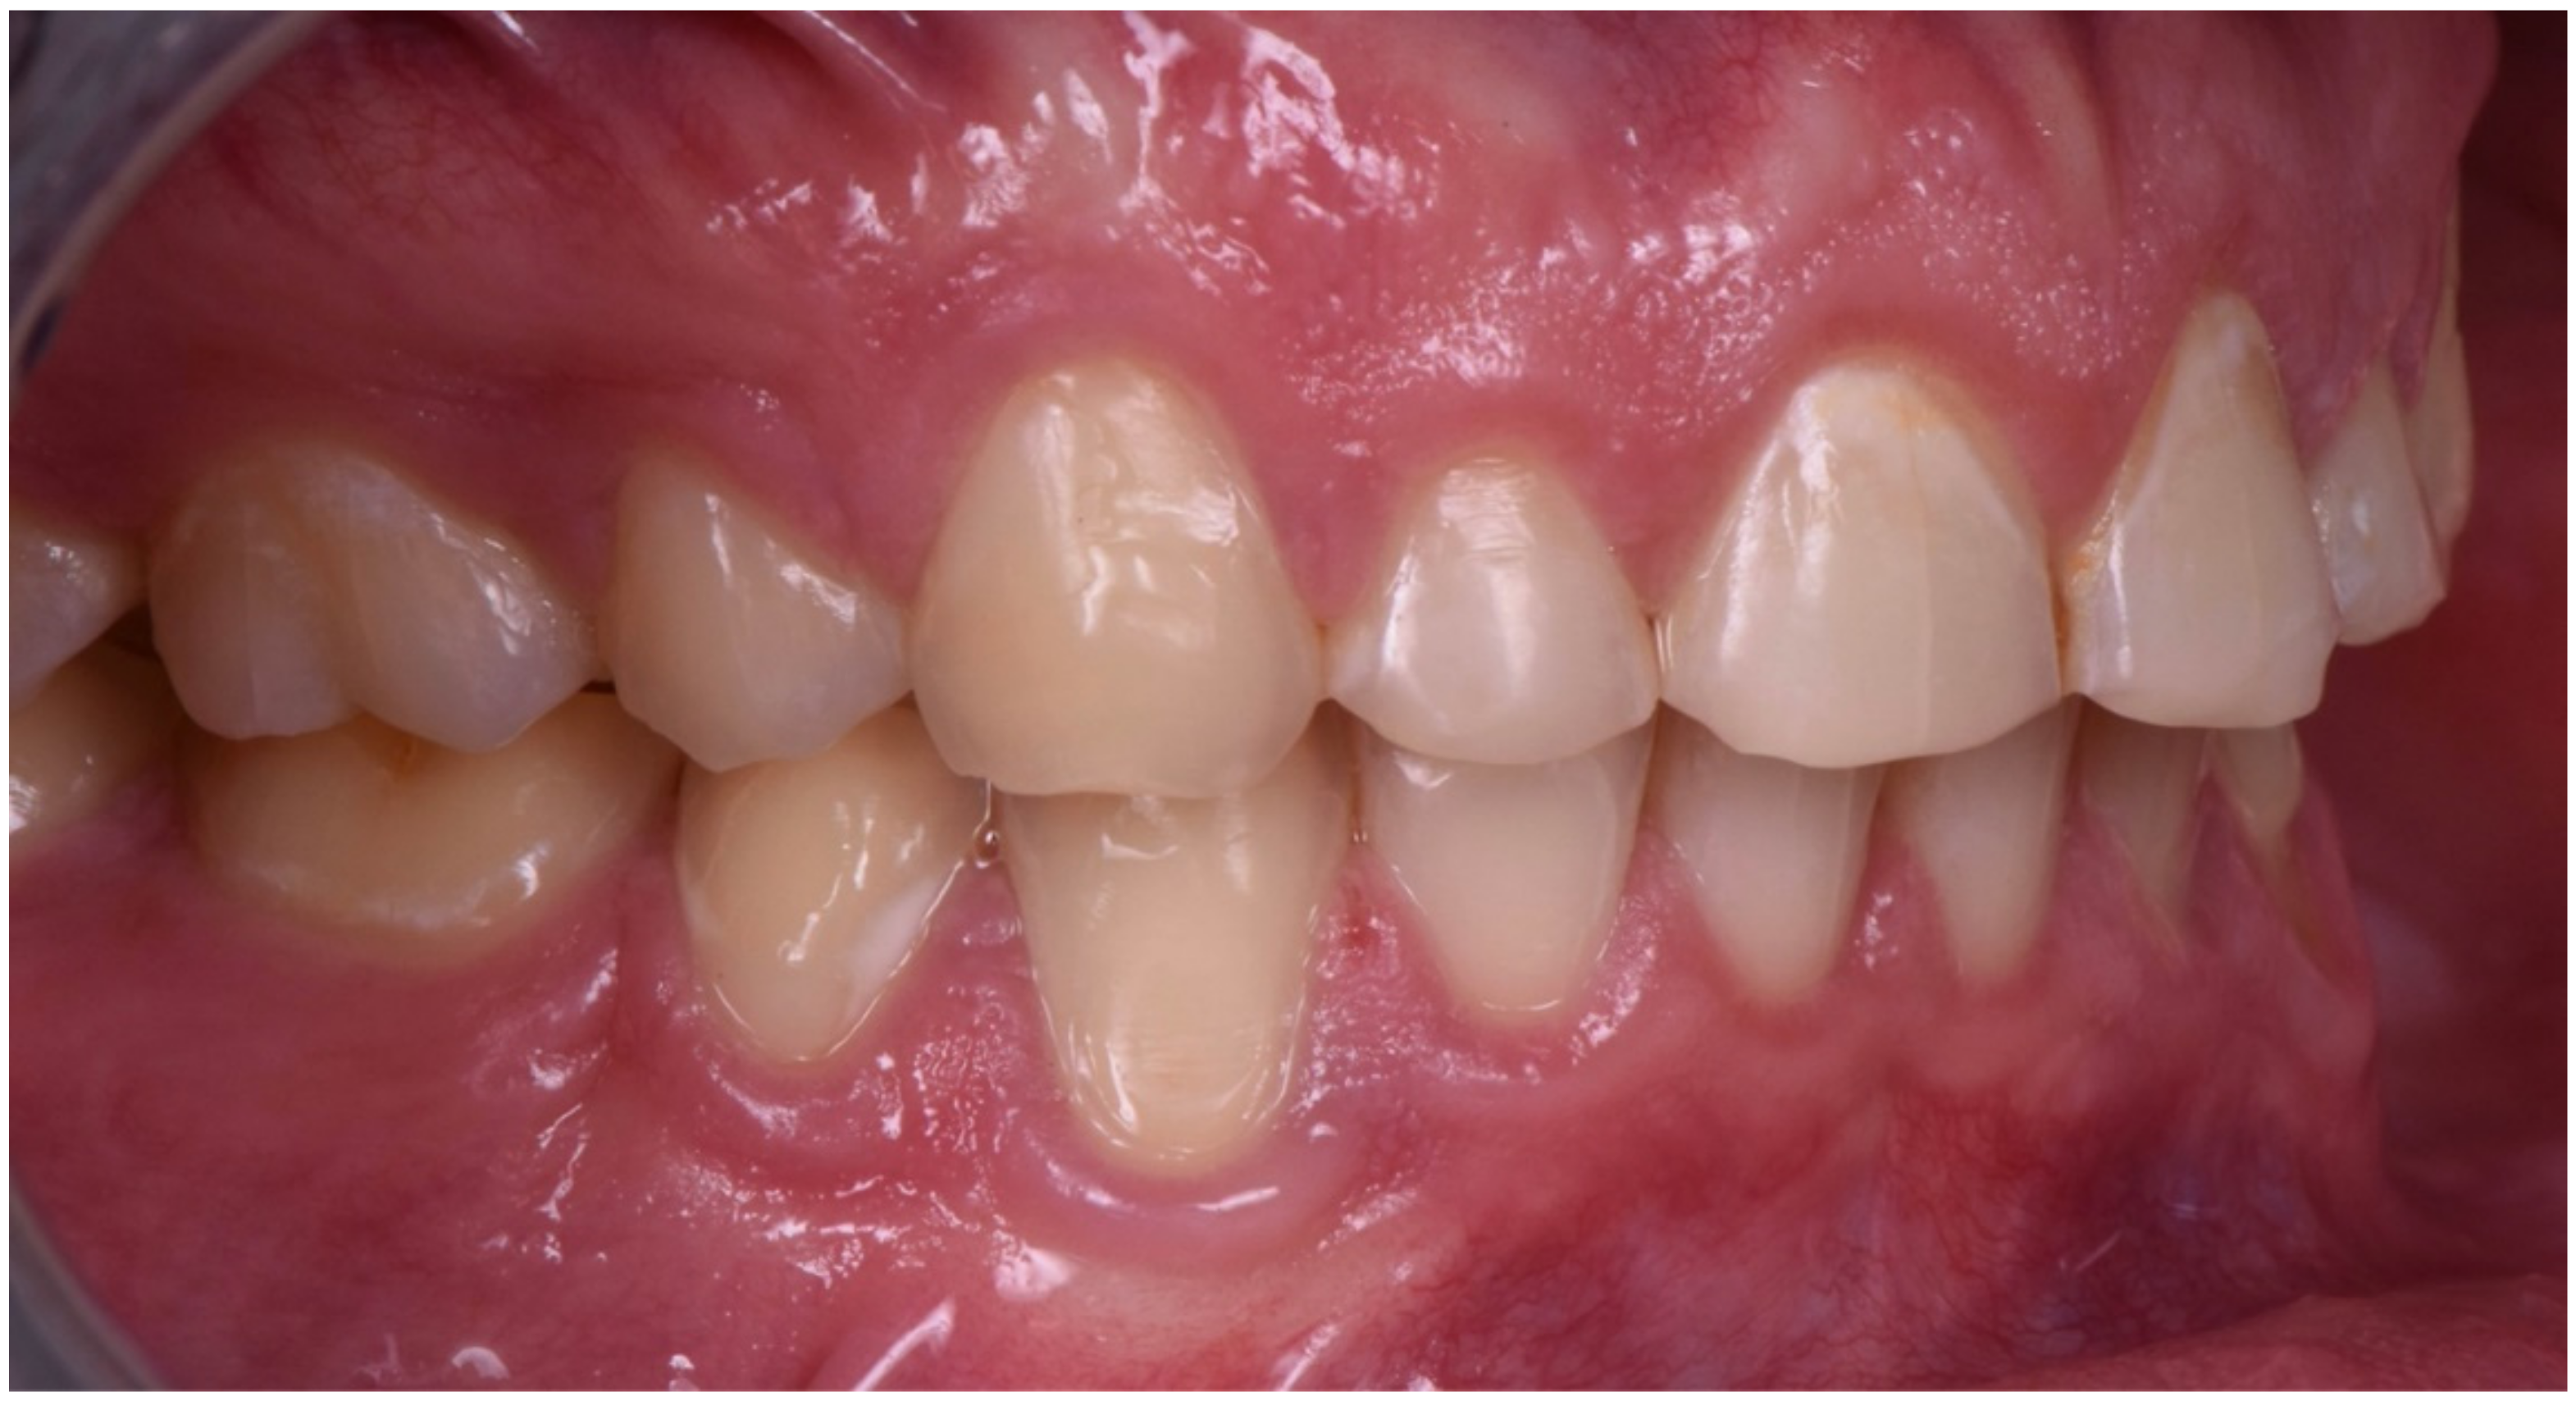

2.2. Restorative Phase